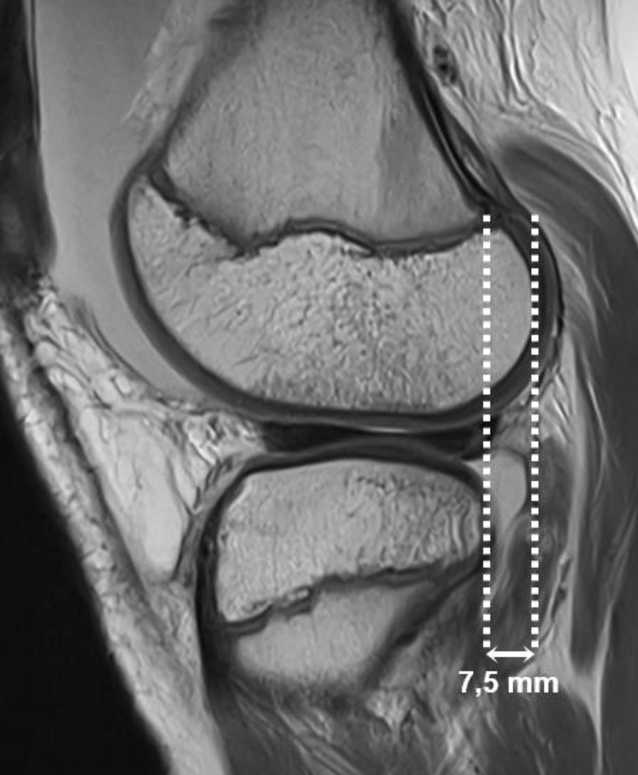

Abb. 3

MRT des Kniegelenks eines 14-jährigen Patienten mit vollständiger Ruptur des vorderen Kreuzbands (nicht abgebildet). Die sagittale protonendichtegewichteten (PD) Sequenz mit zentraler Schichtführung durch das laterale femorotibiale Kompartiment zeigt eine anteriore Subluxation der Tibia gegenüber dem Femur um 7,5 mm (gepunktete vertikale Linien). Dies überschreitet den Normwert von < 5 mm und stellt einen indirekten Hinweis auf eine Ruptur des vorderen Kreuzbands dar